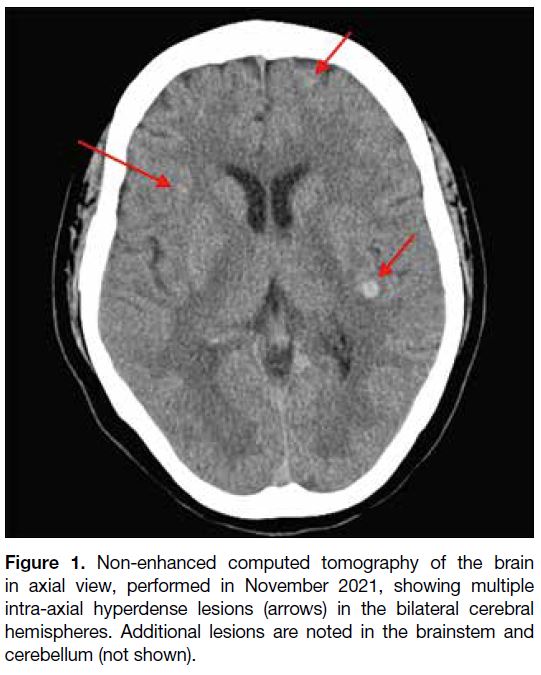

A 56-year-old woman with good past health presented to

the accident and emergency department with dizziness

in October 2021. Initial computed tomography of the

brain revealed multiple hyperdense lesions scattered

across both cerebral hemispheres, the brainstem, and the

cerebellum (Figure 1). Whole-body positron emission

Figure 1. Non-enhanced computed tomography of the brain

in axial view, performed in November 2021, showing multiple

intra-axial hyperdense lesions (arrows) in the bilateral cerebral

hemispheres. Additional lesions are noted in the brainstem and

cerebellum (not shown).